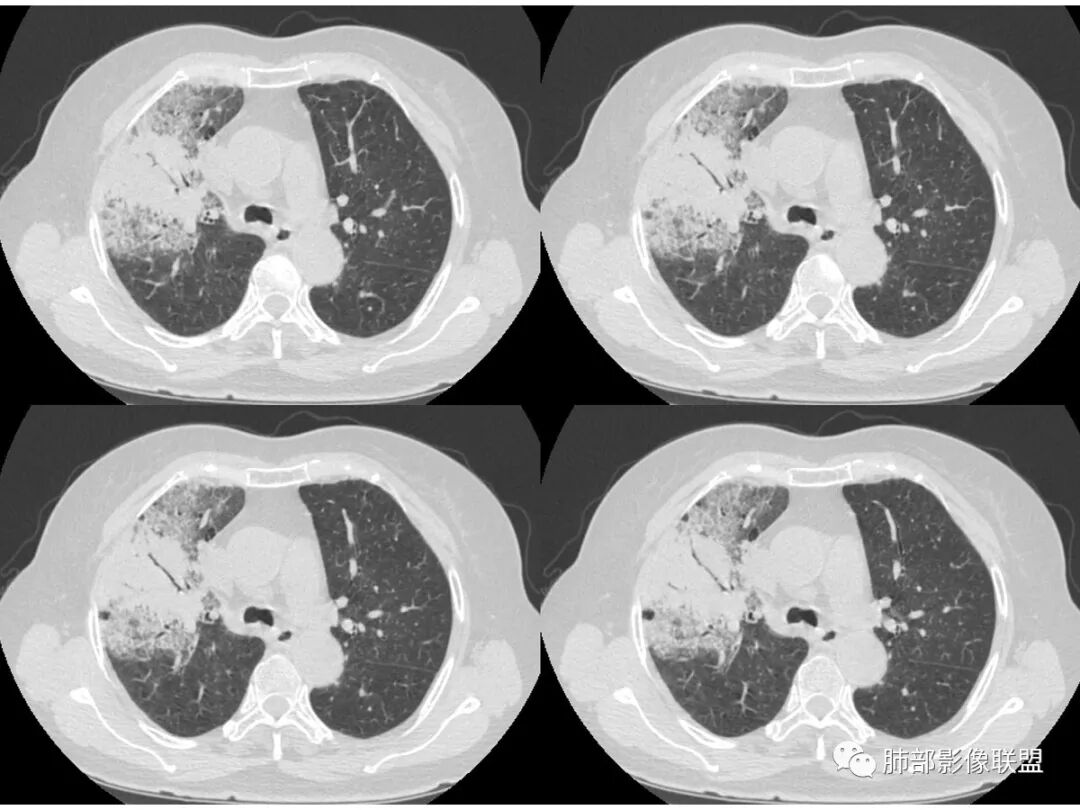

右肺上叶大片状阴影,内见僵硬的支气管,部分支气管轻度扩张,内见一空洞和液平,病灶边缘可见磨玻璃影,首先考虑恶性病变,粘液性腺癌伴感染可能。

老年女性,右肺上叶大片实变及磨玻璃密度影,磨玻璃边缘清晰,内可见小叶间隔增厚,内可见空洞,似可见分隔,叶间裂局部膨隆,纵膈窗,没有增强,枯树枝不明显,肺炎型肺癌可能,鉴别大叶性肺炎,结核?

胸CT:右肺上叶实变内可见支气管充气征,近端支气管狭窄,远端扩张,周围可见毛玻璃影,右肺中叶支气管闭塞,并可见气道壁钙化,右肺中叶体积缩小,实变内可见空洞,并可见气液平面,空洞周围可见毛玻璃样影,右肺下叶支气管开口狭窄,右肺门淋巴结肿大。纵隔窗可见病灶与壁层胸膜间隙增宽,考虑良性病变-----感染性病变------TB?

老年女性,右肺中上叶病灶,血象不高,血沉高,TB dna阴性,上叶尖端病灶,紧贴胸膜,边界似清非清,中间可见实变,内见枯树枝征,首先考虑粘液腺癌可能性大。患者右肺中叶见空洞、气液平,病灶没多发空洞,可见气液平,考虑合并TB感染。

病史老年女,白痰;影像实变,ggo多数边界清,病灶下缘部分不清,枯树枝,支气管近端阻塞、僵硬,病灶跨叶;病灶内空洞,有液平;间质增厚有结节感;肺炎型肺癌大于干酪性肺炎。

老年女性,慢性病程,咳嗽伴白色粘液痰,无发热腹痛,糖尿病,白细胞及C反应蛋白不高,血沉快,铁蛋白高。胸部CT,右肺上叶大片状实变伴磨玻璃密度影,边界不清,边缘局部膨隆,叶裂弧形下坠,实变影宽基底与胸膜相贴;右肺下叶前基底段见类似病灶;右肺中叶不张并空洞形成,空洞内见气液平面;综合考虑右肺上叶及下叶肺炎型肺癌,右肺中叶结核。

老年女性,亚急性起病,右肺上中叶大片状影,跨叶,上叶为主,磨玻璃为主,边界模糊,部分实变,内见空洞影和液气平面,壁光滑,洞内可见结节形成,局部有扩张,首先考虑感染性病变,结核可能;洞内可见结节样病灶,鉴别合并曲霉、肿瘤。

患者老年女性,亚急性起病,胸部CT:右肺上叶大片实变,可内见坏死性空洞,可见mGGO,GGO边缘清晰,局部彭隆,内见支气管充气征,可惜没增强,粘液腺癌要考虑,但病灶明显是内朝外不支持,综合考虑结核,建议查痰找抗酸杆菌、气管镜

老年女性,咳白色粘液痰,右肺跨叶大片高密度影,密度不均匀,其内见支气管枯树征,有空洞,边缘部分清楚,叶间裂有下坠膨隆感。考虑粘液腺癌,鉴别干酪性肺炎